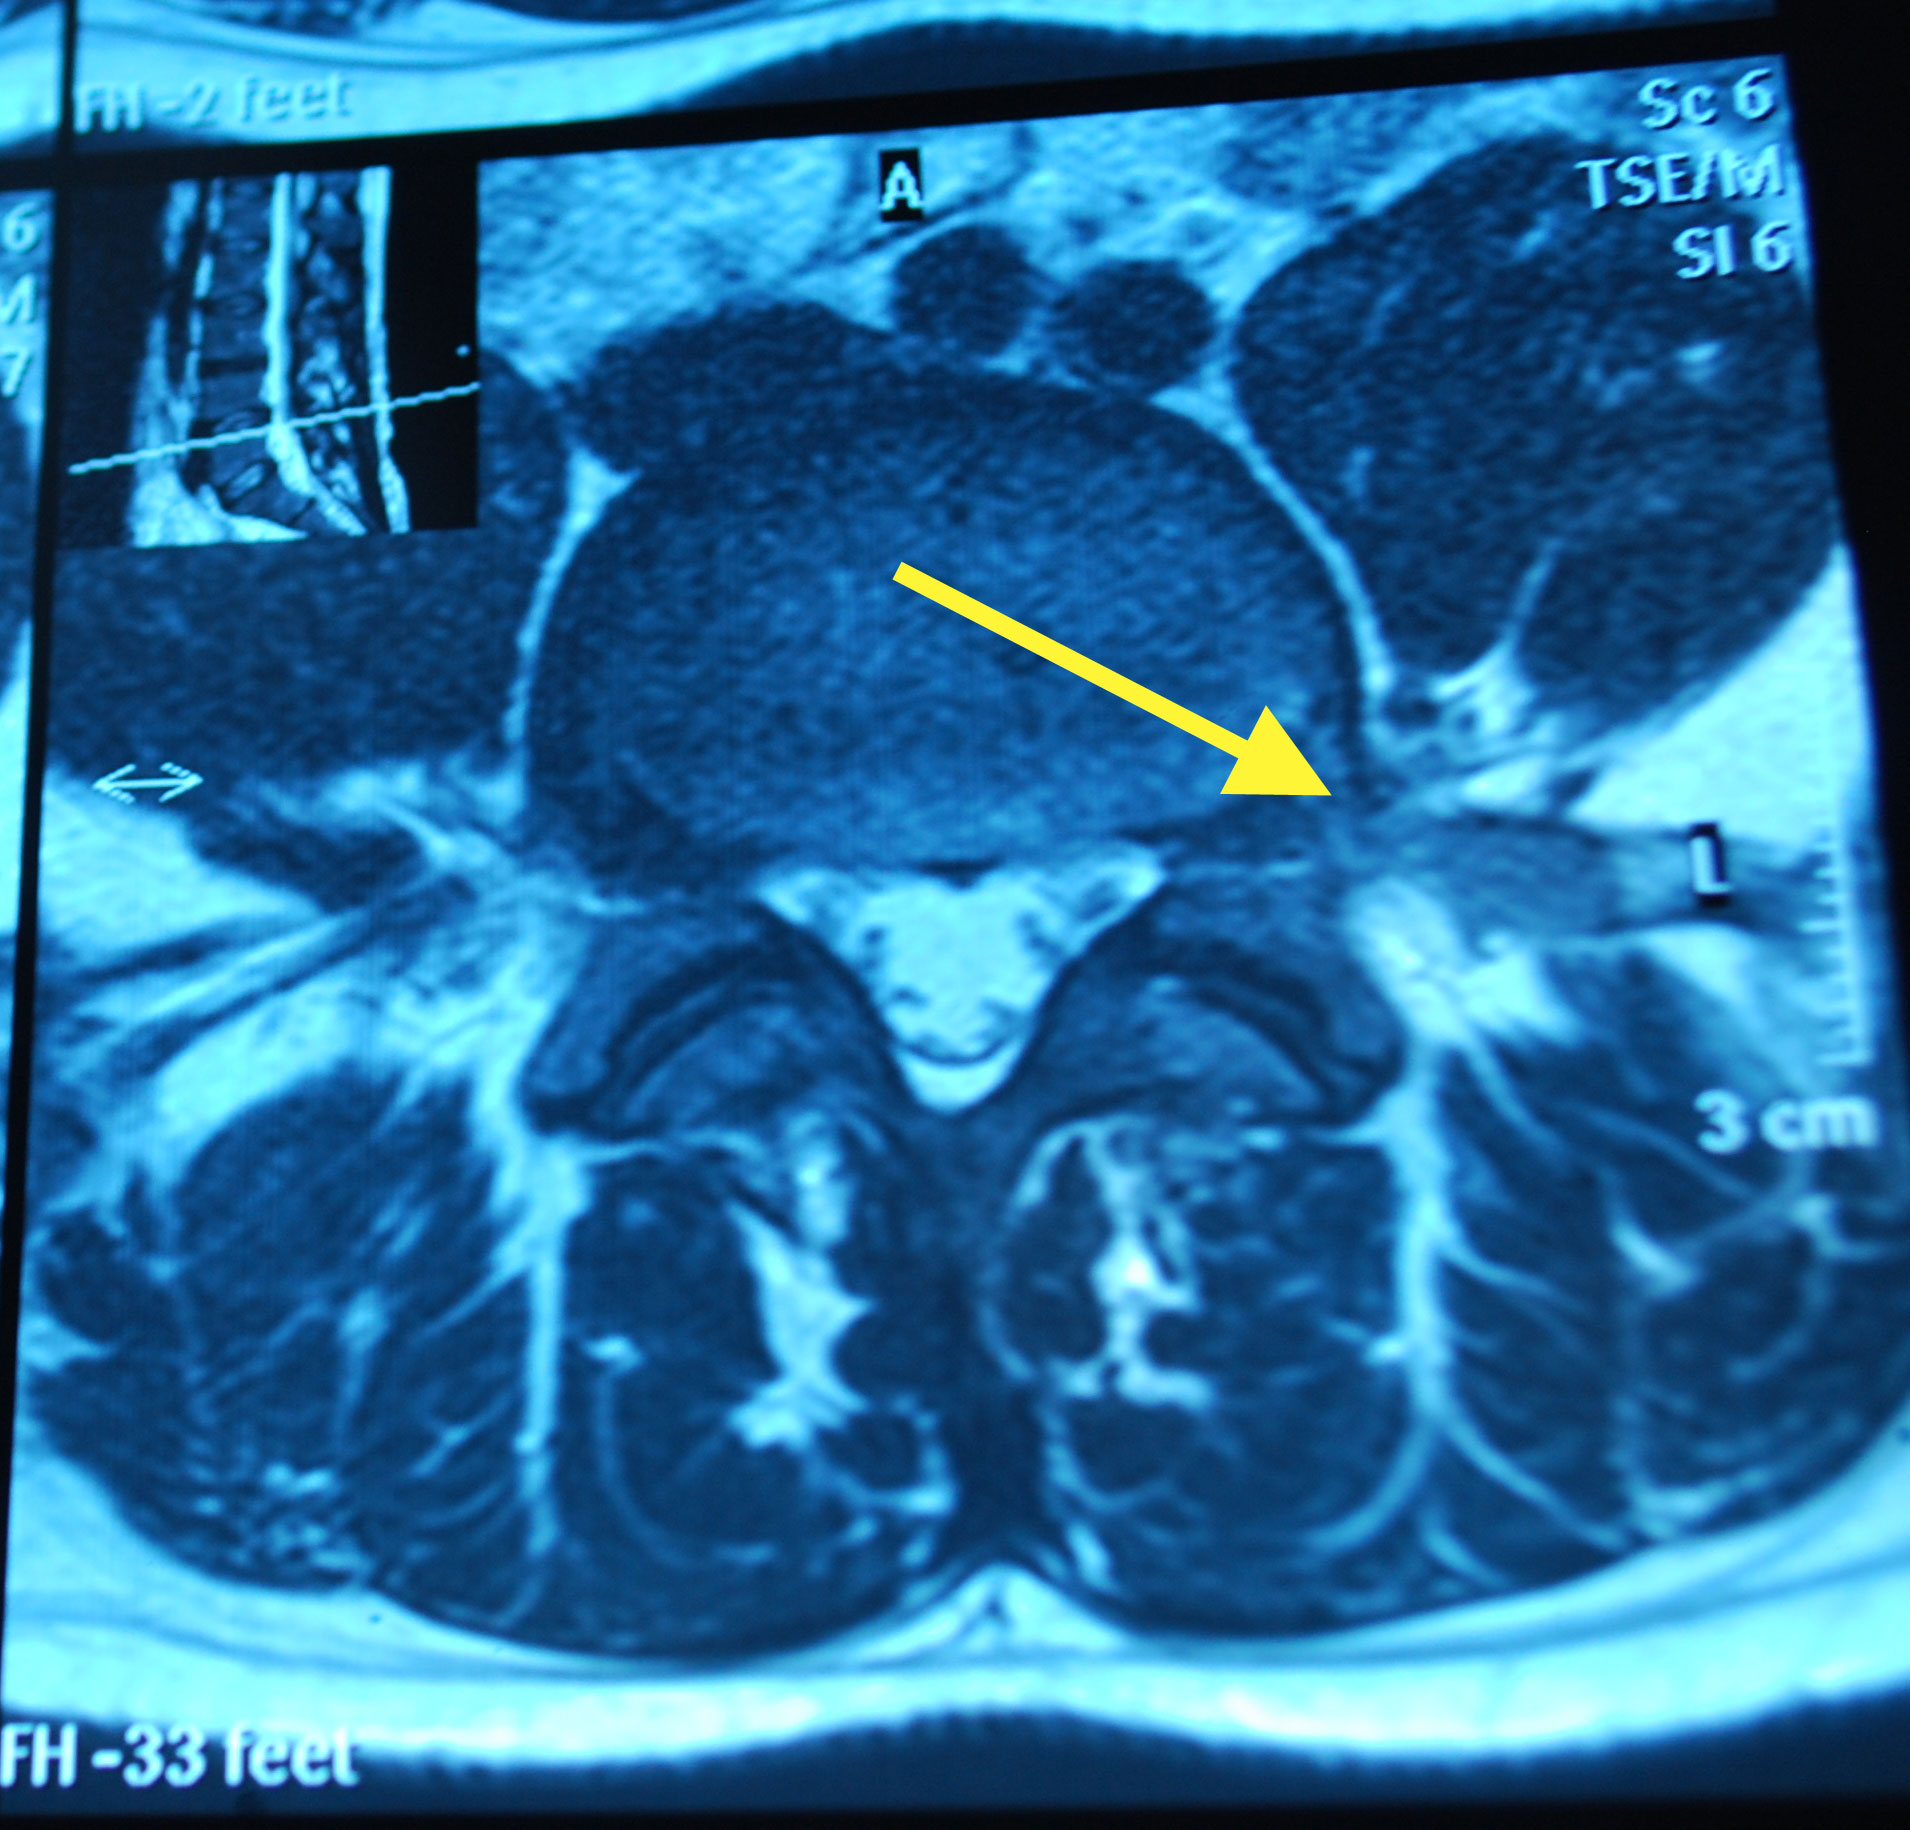

I’ve also come back with copies of my scans. Its very bizarre to sit there and look at slices through your own body. Forget losing weight so you look good in your holiday or wedding photos, try an MRI. There is no turning your best side to the camera or wearing stripes the right way round to hide/accentuate your curves. It shows all your fat, in lovely cross sectional detail. Cath also pointed out that she can see poo in some of the films! Nice…..

Apparently, I’ve also got a dehydrated disc on the next one up (L3/4) which might cause me issues in later life if I’m not careful with impacts, too.